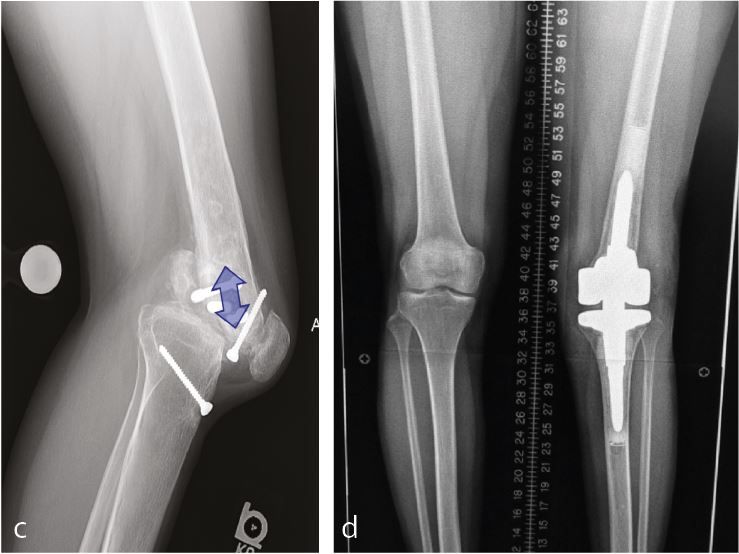

Osteoarthritis in patients with a subluxated or dislocated knee

The stiff and subluxated knee can be a very challenging problems to deal with. First one needs to have a level of suspicion when encountering severe flexion contractures after ligament injuries or knee dislocation. While some posterior subluxation of the femur on the tibia is the hallmark of progressive osteoarthritis in the anterior cruciate ligament (ACL) deficient knee it is important to identify patients with more advanced subluxation/dislocation (Figure 4a) of the femur. In my experience a warning sign is when the insertion of the MCL in the center of the femoral condyle moves beyond a line on the posterior cortical bone of the tibia (Figure 4b). In the presence of stiffness I strongly encourage a preoperative vascular work up. I well remember the one patient that I accidently opened the popliteal artery when trying to mobilize a posterior subluxated femur. Luckily, I had anticipated the complication because of the proximity of the popliteal artery to the posterior condyle of the femur on preoperative MRI imaging (Figure 4c) and the standby vascular surgeon was able to close the vascular injury from anterior enjoying the perfect exposure of an open flexion space with laminar spreaders in place.

The risk of vascular injury and the difficulty of exposure is less when the femur is subluxated anterior, however, this situation is not without difficulties itself. Usually anterior subluxation of the femur on the tibia results in a significant flexion contracture and significant distal femur resection is needed to allow full extension of the knee and balance flexion and extension space. Based on my personal experience I strongly favor a hinge implant for posttraumatic anterior or posterior dislocations of the femur (Figure 5a, b, c, d).

My rational for this implant choice is that in severe anterior dislocation of the femur, often, the insertion of the collateral ligaments gets compromised when additional distal femur resection is needed to allow full extension. In addition, it is difficult to achieve reliable postoperative range of motion when encountering a knee subluxation in the presence of preoperative stiffness (less than 80 degrees arc of motion). Since the combination of a traumatic dislocation is seldom associated with an addition extraarticular deformity stemmed hinge implants can usually be used without problems.